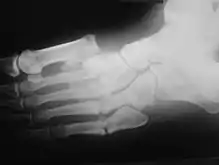

Radiologic findings

First, it is important to recognize that two types of abnormality may be detected. One is termed atrophic, in which there is osteolysis of the distal metatarsals in the forefoot. The more common form of destruction is hypertrophic joint disease, characterized by acute peri-articular fracture and joint dislocation. According to Yochum and Rowe, the "6 D's" of hypertrophy are:

- Distended joint

- Density increase

- Debris production

- Dislocation

- Disorganization

- Destruction

The natural history of the joint destruction process has a classification scheme of its own, offered by Eichenholtz decades ago:

Stage 0: Clinically, there is joint edema, but radiographs are negative. Note that a bone scan may be positive before a radiograph is, making it a sensitive but not very specific modality.

Stage 1: Osseous fragmentation with joint dislocation seen on radiograph ("acute Charcot").

Stage 2: Decreased local edema, with coalescence of fragments and absorption of fine bone debris.

Stage 3: No local edema, with consolidation and remodeling (albeit deformed) of fracture fragments. The foot is now stable.

Atrophic features:

- "Licked candy stick" appearance, commonly seen at the distal aspect of the metatarsals

- Diabetic osteolysis

- Bone resorption